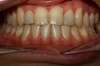

Intra Orale Face